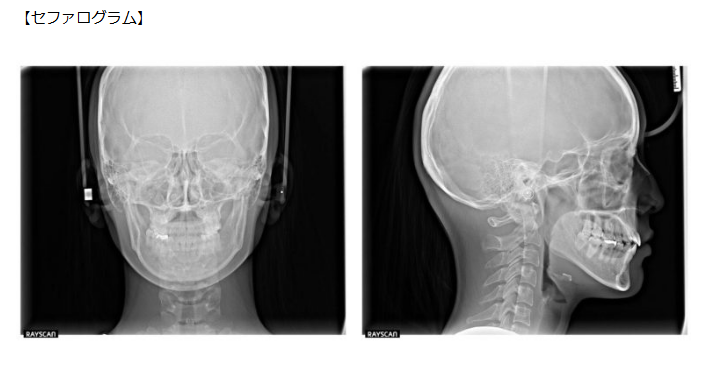

| 設備名 | 役割・特徴 |

| セファログラム(頭部X線規格写真) | ・骨格のタイプや成長方向を分析するために必須 ・頭や顎の骨格、上下の顎のズレ、歯の傾きなどを立体的に把握できる |

あらゆる設備をフル活用すれば、以下のように骨格や噛み合わせを立体的に把握できます。その結果、「感覚や経験だけに頼らない、科学的根拠に基づいた矯正」を行うことができるのです。

| 歯列矯正に必要な設備 |

| ・セファログラム

・光学3Dスキャナー(矯正前後のシミュレーションも可能)

・歯科用CT

・パノラマレントゲン

|

※表内の画像について出典:ミライズ矯正歯科南青山